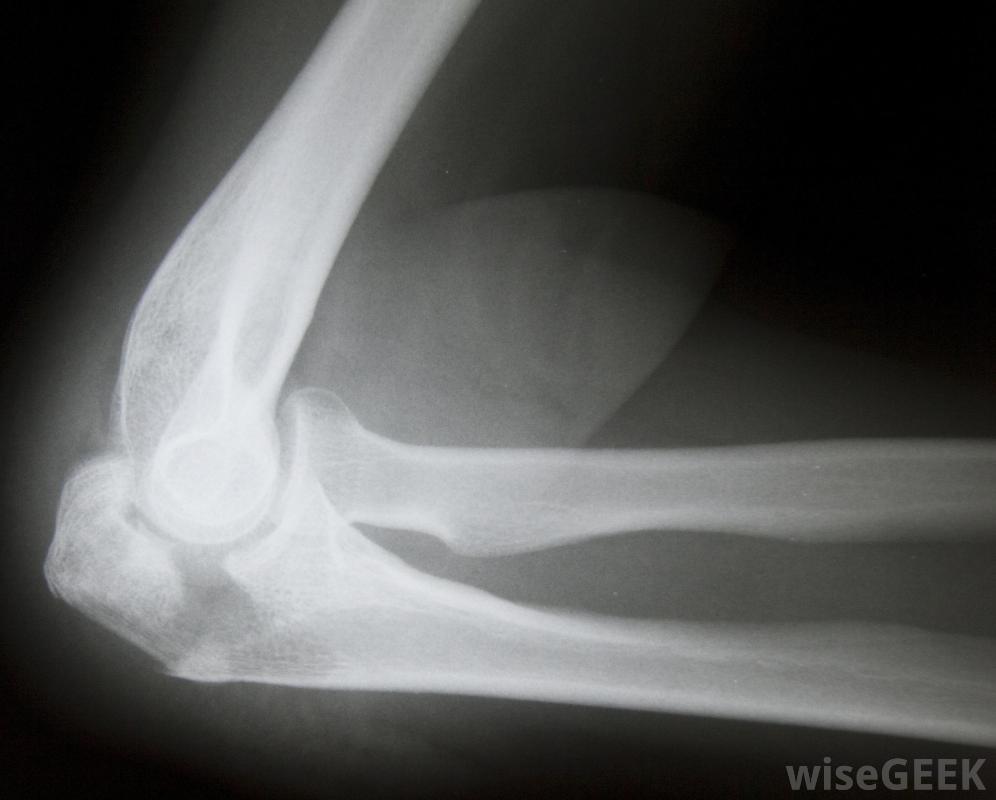

髁突是骨的圆形部分,通常位于关节内,并与另一块骨头相连。当这部分骨头因撞击或扭曲而破裂时,髁状突骨折。这种情况可能发生在肘部、膝盖或身体中存在髁状突的其他关节处。治疗髁状突骨折通常从固定受影响的关节或骨骼开始,以防止进一步的损伤和减轻疼痛。最初的治疗通常包括米饭过程,即休息、冰敷、压迫,为了正确诊断髁状突骨折,需要进行X光检查受伤后应立即咨询医生,但在试图移动患者之前,必须正确固定受影响区域。轻微的髁状突骨折可以很容易地治疗,但更复杂的骨折需要更密集的治疗,因此,最好尽量防止髁突过度损伤。为了正确诊断髁突骨折并评估损伤的严重程度,可能需要进行x光检查。如果没有骨碎片,通常可以避免手术,但如果骨头的任何部分已经分离,手术可能是必要的,以清除骨碎片和可能的其他受损组织

如果骨的任何部分与髁状突骨折分离,则可能需要进行手术。轻度至中度髁状突骨折通常会使用消炎药物和固定医生可能会在愈合过程中使用硬石膏来防止骨头移动。这种石膏可以保护骨骼不受进一步的伤害,防止移动,并增加刺激血液流动的压力,加快愈合过程。还可以开止痛药,由于髁状突骨折可能是相当痛苦的情况,这取决于损伤的严重程度。